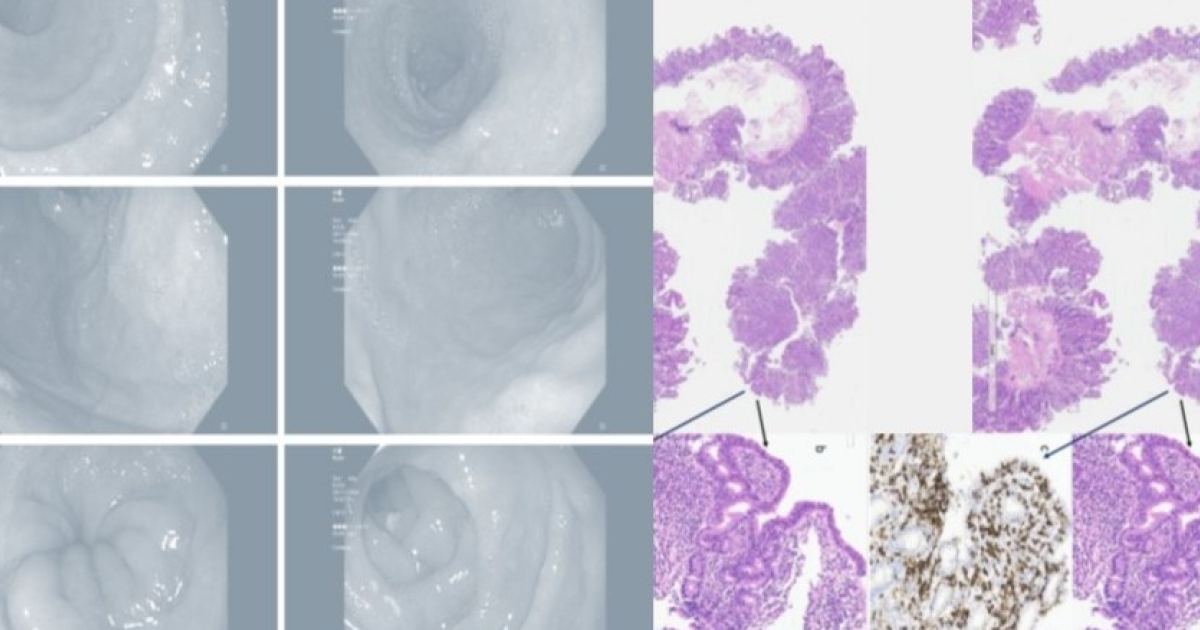

Итальянские врачи описали случай тяжелого поражения кишечника у пожилой пациентки, которая на протяжении года принимала олмесартан. Препарат вызвал у женщины выраженную атрофию ворсинок двенадцатиперстной кишки, что привело к развитию спру-подобной энтеропатии и выраженной водянистой диареи. После замены препарата произошло скорое восстановление функции кишечника. Случай описан в BMJ Case Reports....